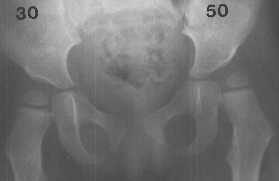

A 2 year and 3 month old girl presented for evaluation. The child was

the 3 pound 5 ounce product of a 30 week gestation which was complicated

by a low birth weight and respiratory distress at birth. She was able to

sit alone and just started to crawl at 11 months. Hip abduction was 25

degrees on each side with the hips and knees extended. Popliteal angles

were 10 degrees, bilaterally. In the prone position with her hips extended,

she has 60 degrees of internal rotation bilaterally and 40 degrees of external

rotation on the right and 60 degrees of external rotation on the left.

She had a negative Barlow test.

This

x-ray of her hips is slightly abnormal.